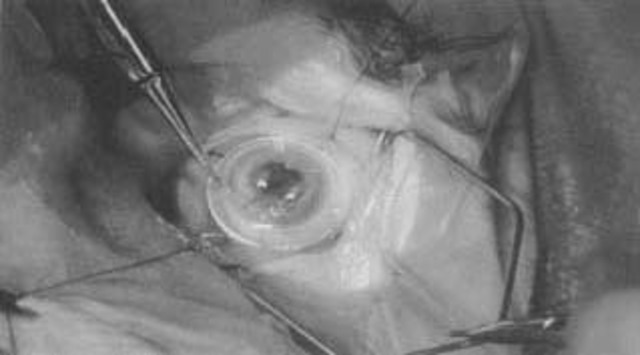

• cornea transplant

cornea transplant

In 1905 the first successful cornea transplant was performed